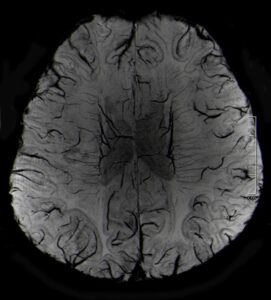

„Der neue MRT ermöglicht dank der sehr hohen Auflösung detaillierte Einblicke in den menschlichen Bewegungsapparat, zeigt präzise die Stoffwechselprozesse im Gehirn und hilft außerdem bei der Darstellung neurologischer Krankheiten“, sagt Prof. Dr. Michael Uder, Direktor des Radiologischen Instituts des Universitätsklinikums Erlangen. Für seinen Kollegen, Prof. Dr. Arnd Dörfler, Leiter der Neuroradiologischen Abteilung des Universitätsklinikums Erlangen, zeigt der neue MR-Scanner besonders bei Gehirnuntersuchungen seine Vorteile: „Bei 7-Tesla sind Gehirnschädigungen dank der besseren Auflösung und des deutlich stärkeren Bildkontrasts viel klarer zu erkennen.“ Anwendungsbeispiele hierfür seien Multiple Sklerose, Hirntumoren oder Metastasen, Epilepsie und Demenz, bei denen die höhere Detailauflösung neue diagnostische Möglichkeiten bietet, die bei niedrigeren Feldstärken so nicht möglich wären. „Viele Erkrankungen können so wahrscheinlich besser und schneller erkannt und damit effektiver behandelt werden“, so Prof. Dörfler

Der Grund für die bessere Auflösung der Untersuchungsbilder ist die höhere Messgenauigkeit des neuen Systems. Diese hängt mit der Feldstärke des Magneten im MRT zusammen. Je stärker das Magnetfeld ist, je genauer ist die Bildgebung. Da die Feldstärke am 7-Tesla-MRT mehr als doppelt so hoch ist, wie die der heute gebräuchlichen 3-Tesla-MRT, können nicht nur feinste Gewebestrukturen besser sichtbar gemacht werden, sondern auch Stoffwechselprozesse im Gewebe. Am Standort Erlangen werden die Möglichkeiten des neuen Ultrahochfeld-MRT jetzt intensiv weiter erforscht.